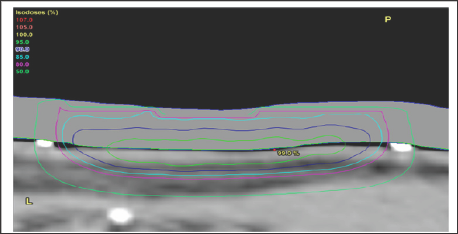

b) The use of computer tomography (CT) planning scans. MVT enables the use of computer tomography (CT) planning scans taken in the treatment position, and planning systems. The volumes to be treated and avoided are contoured by the radiation oncologist on these scans. Doses are prescribed for each volume. Dose Volume Histograms (DVHs) can be constructed and doses per volume on each individual patient plan can be compared to standardized doses for CTV and PTV and OARs. These standardized doses are known to predict cure for tumour bearing volumes and are associated with acceptable side effects in normal tissue volumes. Technology with the planning system is then used to optimize the plan to achieve these bench marks, ensuring tumour cure and normal tissue tolerance at the end of treatment (Figure 9).

Figure 9: Photographs and CT plans of a patient preparing for VMAT.

A: Mark up of a scalp field at planning showing areas of gross tumour within the area of ESFC.

B: CTV is contoured on the planning scan. Red volume represents ESFC.

C: The resultant dosimetry avoiding brain. The dose homogeneity is uniform throughout the target. The dose profile across the field is uniform with no need for junctioning radiation fields. Green volume represents gross tumour.

C)The use of Intensity modulated radiotherapy (IMRT). IMRT, using automated multileaf collimators in the head of the linac, enables the intensity of the beam to be modified during beam-on time, sculpting the dose to the contoured volumes. Prior to this advance radiotherapy was initially Two Dimensional (2D) and based on fields. The application of CT technology in planning accelerated the uptake of progression to Three Dimensional Conformal Radiotherapy (3DCRT) with the concept of volume treatment. However, RT still came in "blocks" IMRT allowedtreatment around curves, especially sparing dose to OARs in the concavity of a volume requiring treatment (e.g. brain underneath a scalp)

The significance of these advantages for skin cancer is that radiotherapy can now treat large curved convex surfaces, such as those found in ESFC. Large convex surfaces of ESFC can be found covering anatomical sites such as the scalp, forehead, cheeks, forearms, legs, chest, upper back, and shoulders, VMAT can now be used to treat these skin surfaces with definitive MVT photon RT (Figure 9). These advances have overcome the problems of traditional RT. The dose can now be more uniform throughout the target, with no need for junctioning radiation fields.